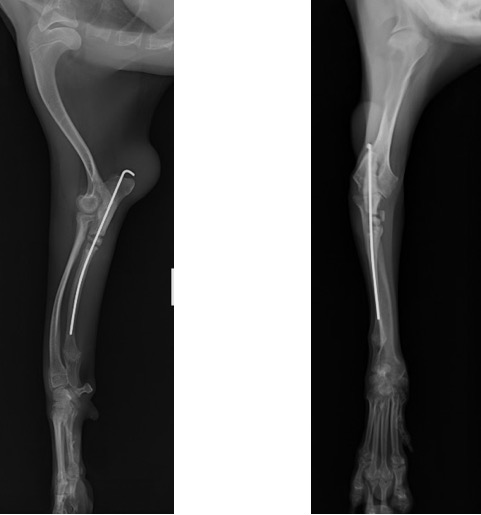

術後の側面像と頭尾側像 (骨切り後に尺骨のアラインメントを合わせるために髄内ピンとして1.2mm K-wireを刺入しました)

術後の側面像と頭尾側像 (前例と同じく髄内ピンとしてK-wireを刺入したのちに切り取った骨片を破砕し、骨切部分へ再移植しました。)